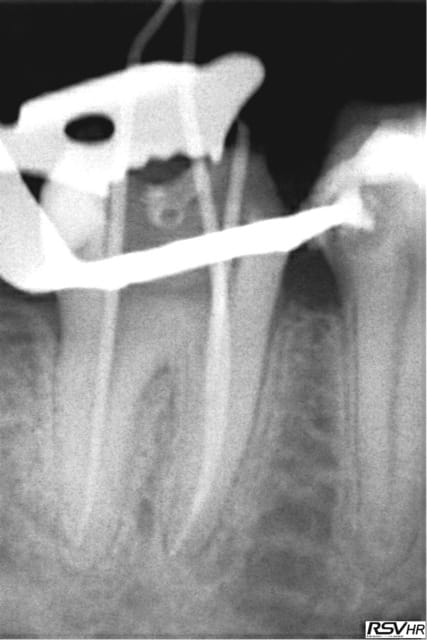

Tiens les endos de la semaine, que d'apex défoncés !-))

La 47 en fin le distal est obturé au système B (bouchon apical) et au mac spaden pour la partie coronaire, tu vois la différence à la radio ? Alors l'apex défoncé il faut avoir l'oeil ! peut etre mais à 25 centièmes et à conicité 6 %........-))

Ce sont des cones dentsply mais pas les réciprocs. je les scelle au tubuli seal en pompant un peu ( d'ailleurs sur la 25 ci dessous qui avait un 4eme ca a fait un dépassement preuve que ca fuse) je les coupe ensuite au système B avec le pluggeur qui sert à faire le bouchon apical.

Tres pratique d'ailleurs pour faire le cas échéant les tenons dans la séance de l'endo, l'empreinte et la provisoire dans la foulée.